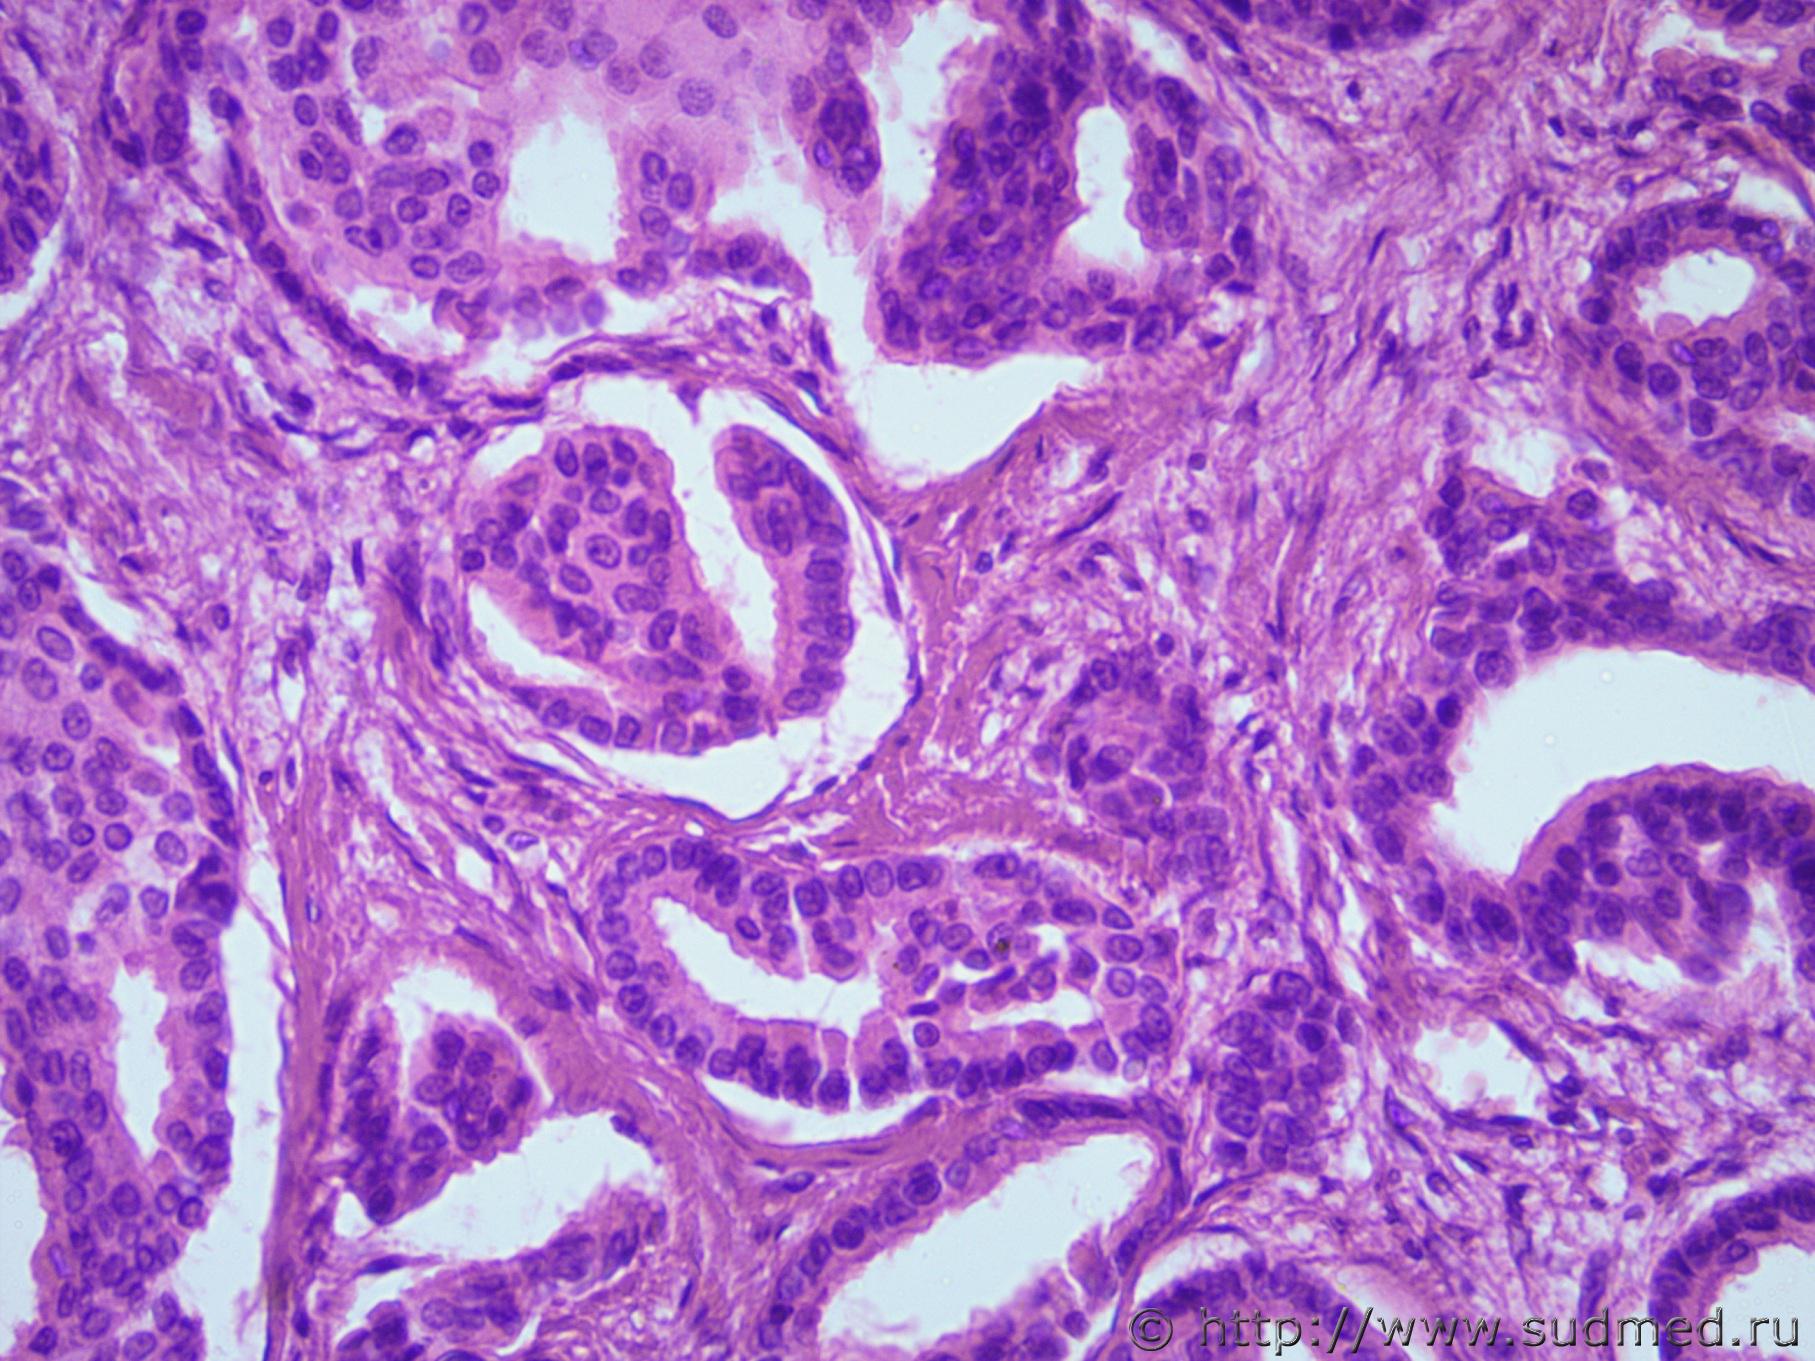

Опухоль грудной железы |

IVANNES Опухоль грудной железы 21.03.2017 - 11:18

Медик Протоковый рак. 21.03.2017 - 17:38

sudmedpatolog Протоковый рак.

Не успела сама себя исправить ... 21.03.2017 - 17:42

IVANNES Я тоже склоняюсь к инвазивному протоковому раку. К... 22.03.2017 - 09:16

Медик Показал коллегам.

Мнение их : на первом фото дольк... 22.03.2017 - 09:43